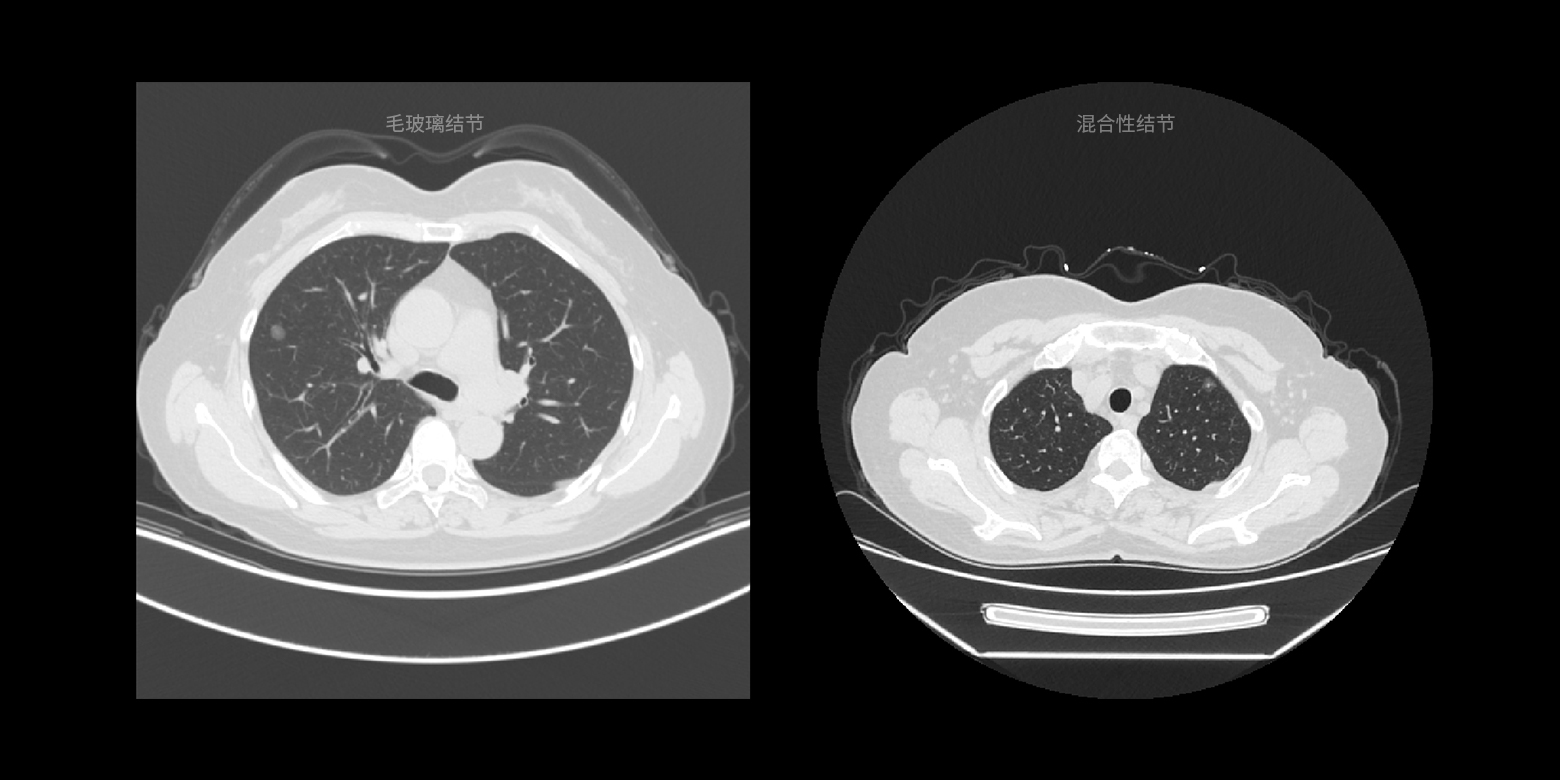

- 04病灶類型鑑別

04 / 05

病灶類型鑑別

根據國際通用的診斷指南以及頂級醫生的診斷經驗,針對臨床診斷的病變類型進行快速鑑別,降低相似病變的誤診概率。

04 / 05

病灶類型鑑別

根據國際通用的診斷指南以及頂級醫生的診斷經驗,針對臨床診斷的病變類型進行快速鑑別,降低相似病變的誤診概率。